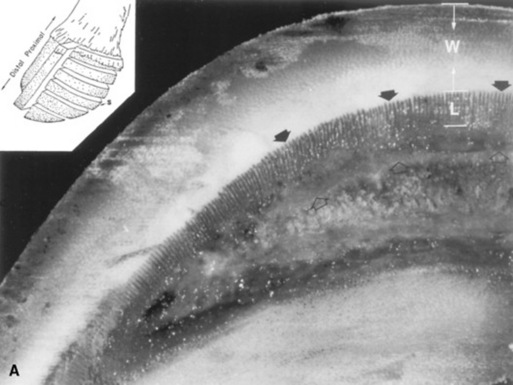

Peracute cases may have total degeneration of the secondary epidermal laminae, which causes a separation between the primary epidermal laminae of the hoof wall and the collagen fibers of the corium. Abscessation may occur in the necrotic laminae or subsolar tissues. The distal phalanx may sink or may be rotated ventrally with respect to the hoof capsule, and the tip may penetrate the sole (Fig. 38-31). Severe cases are accompanied by fractures of the solar margin, osteomyelitis, or severe resorption of the distal phalanx. The necropsy findings generally demonstrate a variable degree of elongation of the epidermal laminae, which depends on the severity and duration of the problem (Fig. 38-32).

image image

Fig. 38-32 A, Section of a healthy foot. The section was cut parallel to the coronary band, midway between the coronary band and the bearing surface of the hoof wall (inset, S). The length of the epidermal laminae (L) is approximately 33% of the thickness of the hoof wall (W) in normal horses. The distance between the dorsal cortex of the distal phalanx (open arrows) and the inner surface of the hoof wall (arrows) is normally less than 75% of the thickness of the hoof wall. B, Foot section, cut in a manner similar to that of A, from a foot of a horse with moderate laminitis. Note the increased length of the epidermal laminae (L). The increase in epidermal laminar length has allowed the distance between the dorsal cortex of the distal phalanx (open arrows) and the inner surface of the hoof wall (arrows) to become almost as large as the thickness of the hoof wall (W). C, Foot section, cut in a manner similar to that of A, from a foot of a horse with severe laminitis. Note the marked increase in length of the epidermal lamina (L). The distance between the dorsal cortex of the distal phalanx (open arrows) and the inner surface of the hoof wall (arrows) is abnormally increased to almost three times the thickness of the hoof wall (W).